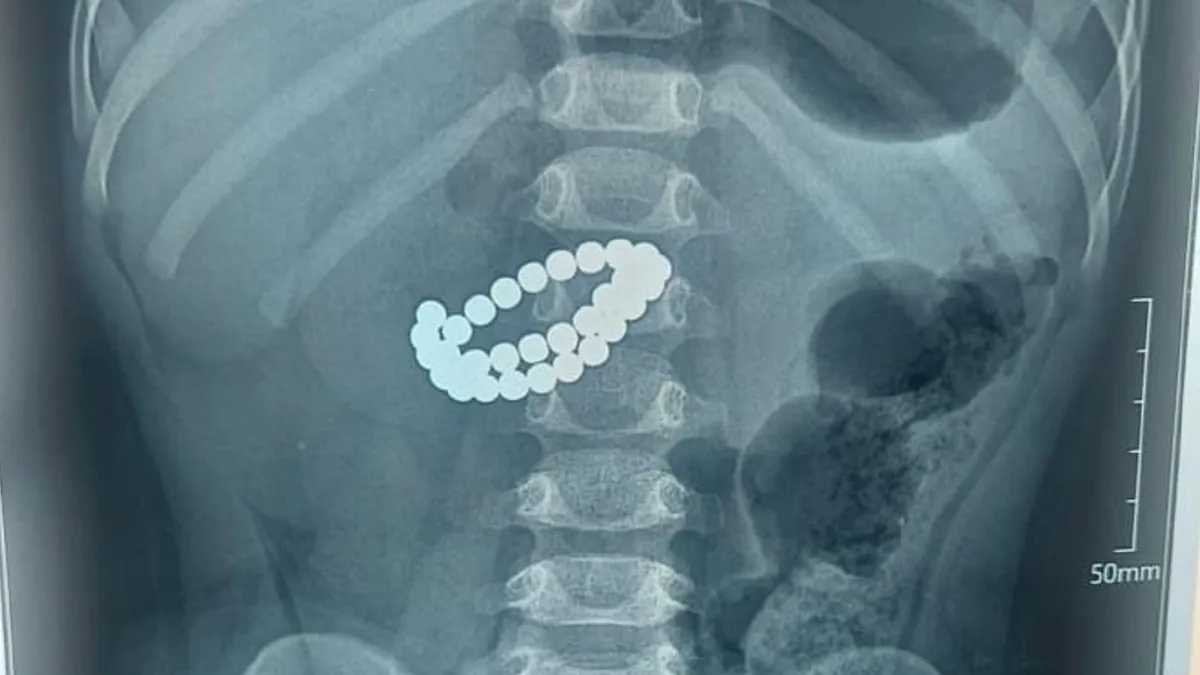

Рентген пострадавшего ребенка

Рентген. Фото: акимат Алматы

В Центре детской неотложной медицинской помощи Алматы ребенку провели экстренную операцию - он проглотил 31 магнит, передает NUR.KZ со ссылкой на пресс-службу акимата мегаполиса.

Врачи установили диагноз: инородные тела кишечника - 31 магнит, множественные перфорации тонкой кишки, диффузный каловый перитонит.